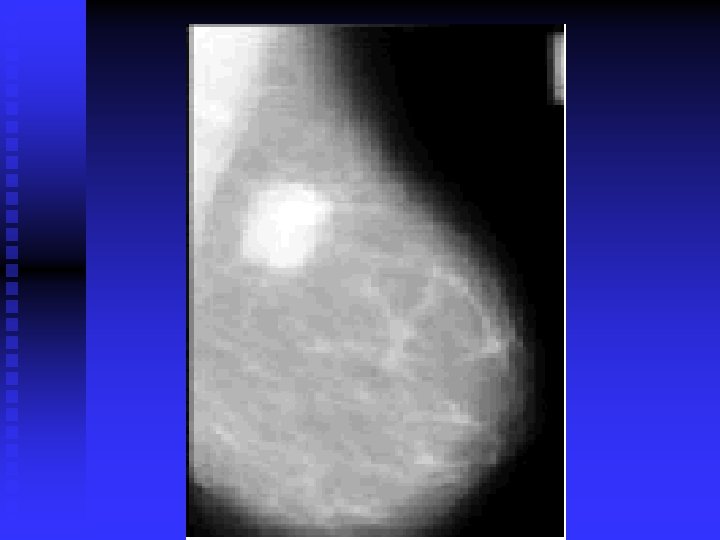

28 -year-old woman 4 months postpartum and not breast-feeding. The right breast contains a

28 -year-old woman 4 months postpartum and not breast-feeding. The right breast contains a large mass (arrow) palpable on physical examination. The left breast contains two smaller nonpalpable masses (arrows) with microcalcifications. All three lesions were breast cancers.